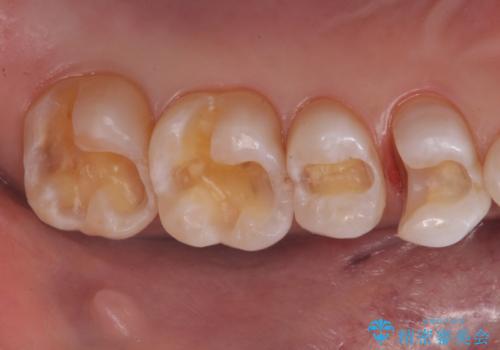

- 奥歯の詰め物のやり替え希望で来院されました。

残る歯の量が多かったためすべてインレーでの治療となりました。

笑った時にチラついていた銀歯がなくなり大変喜んでいただけました。